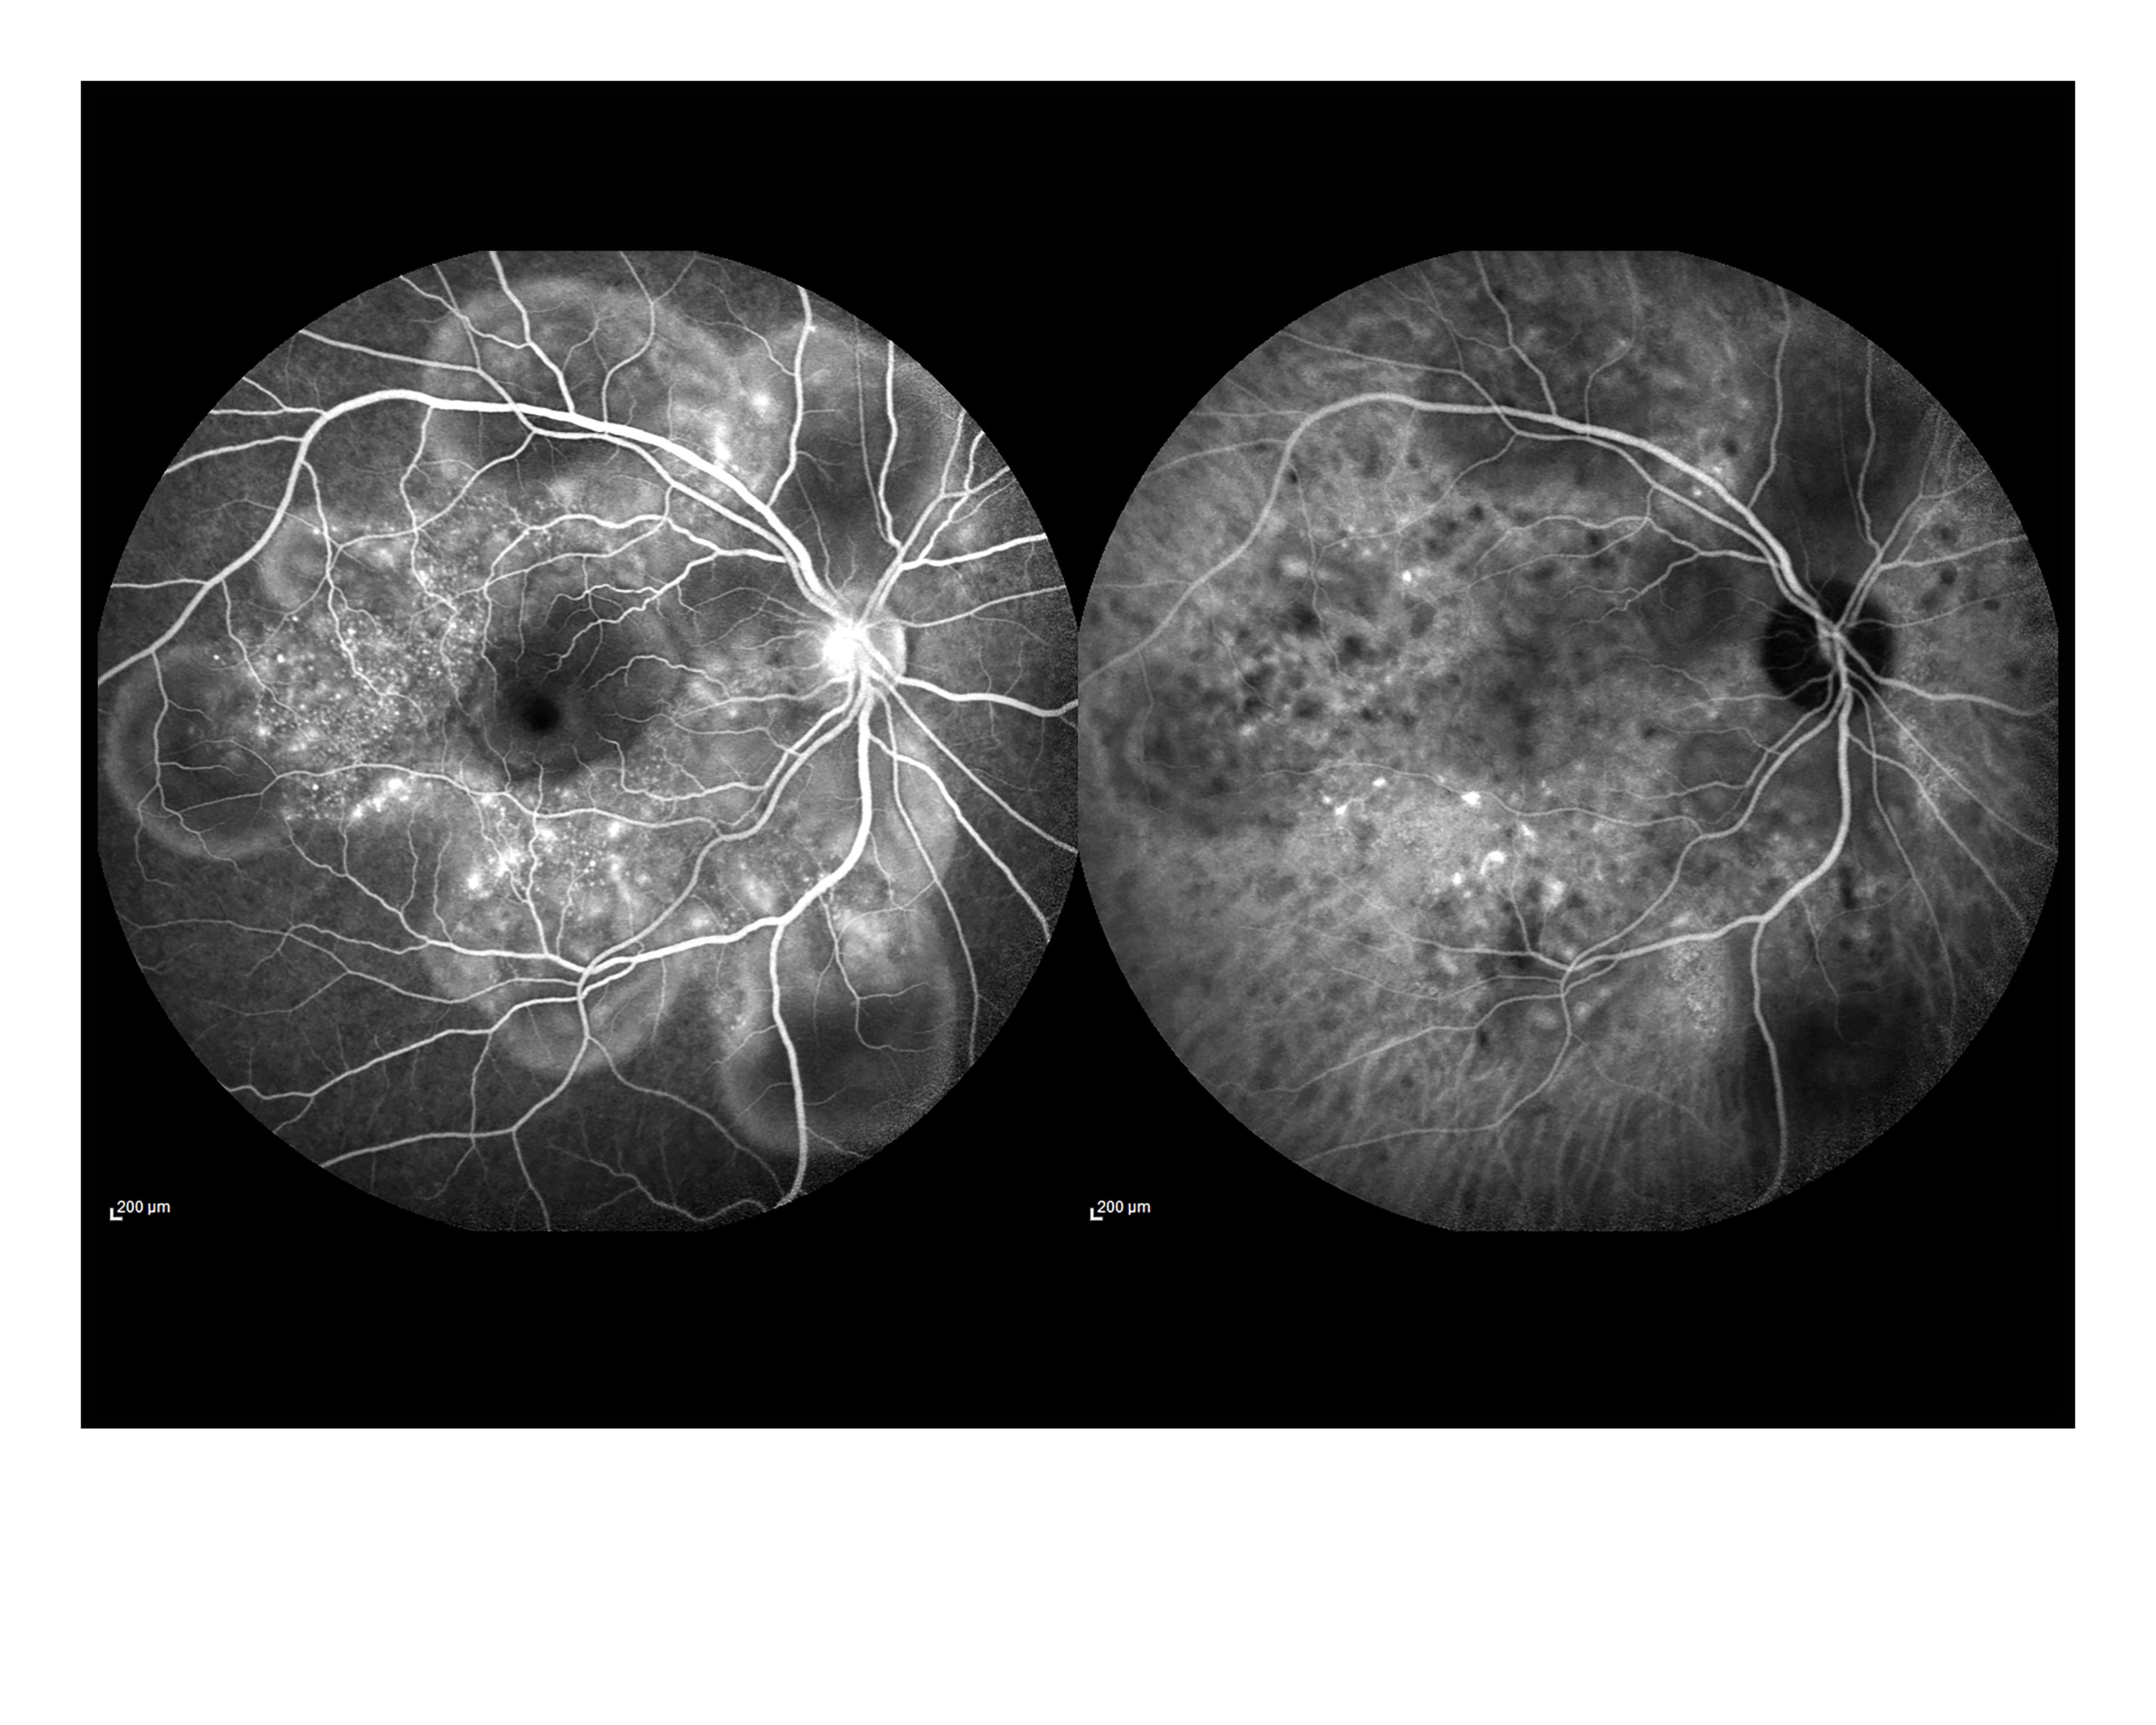

Vogt Koyanagi Harada Disease Presented by Nipan Yomandee This photograph received First Place in the category "Indocyanine Green Angiography" and was displayed in the 2024 OPS Exhibit. Filed Under Cornea OPS Photo